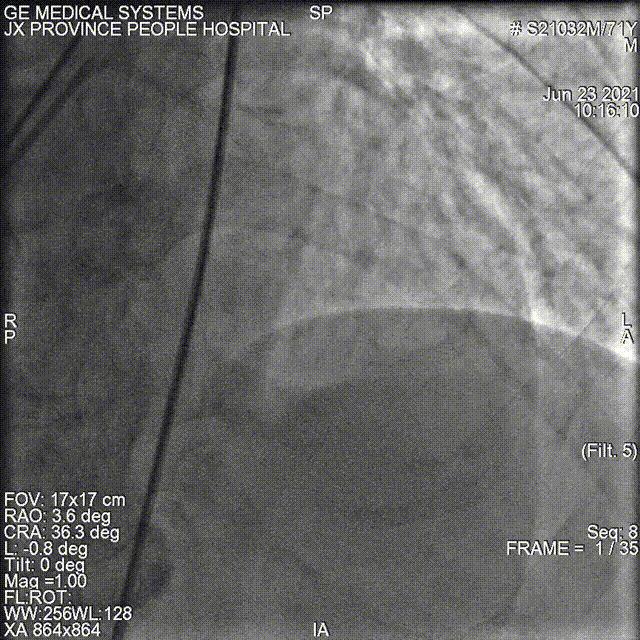

冠脉造影